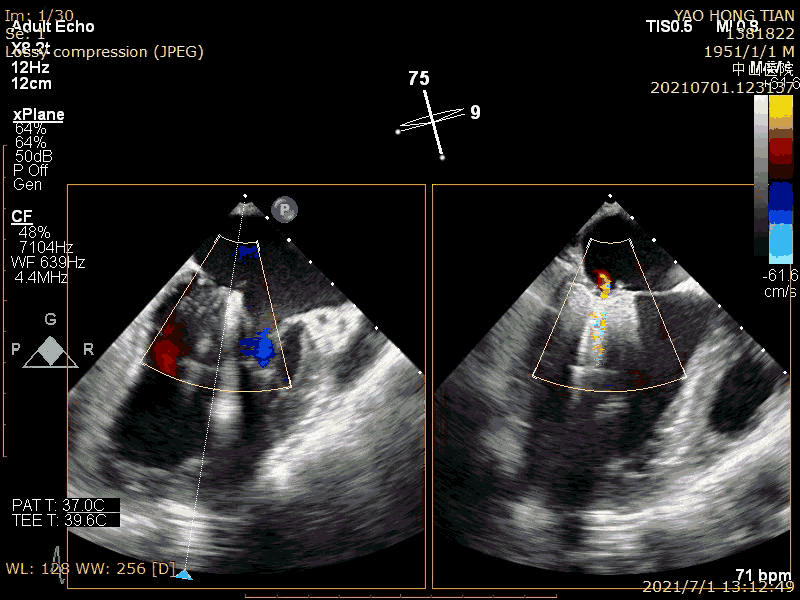

最后效果(轻微反流),最大/平均压:差4/1mmHg

在二尖瓣反流病因构成中,功能性反流更常见,其为器质性反流的3-4倍(Am Heart J. 2018 ;203:39-48.)。而房性功能性二尖瓣反流(AFMR),在功能性反流里也是非常常见,笔者估测可占到40%。本例结果显示ValveClamp 对AFMR效果良好,操作简便,导管操作时间不到20分钟,总手术时间不到50分钟,术后轻微反流。特别提到的是,本例反流范围达13mm,且反流为多束。一个夹子ValveClamp即起到完美效果,而其他产品很可能需要2-3个夹子,这充分体现了ValveClamp“以小治大” 的设计优点。仅使用单个夹子,可以降低手术难度和手术时间,降低耗材成本。